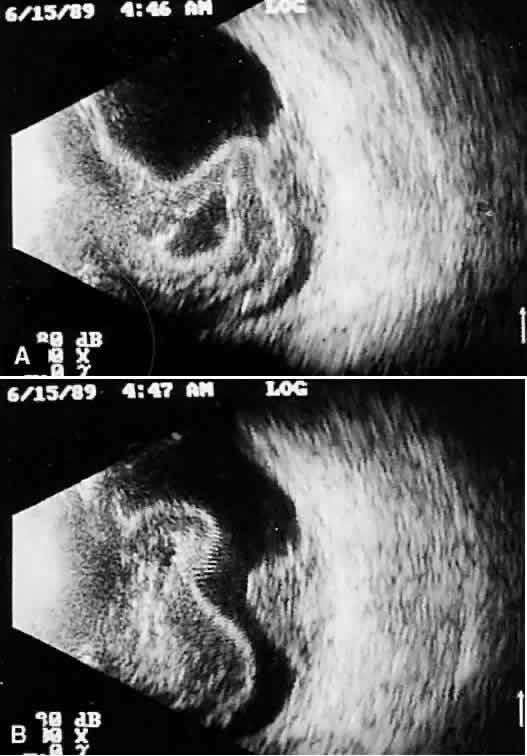

Choroidal malignant melanoma, perhaps the most widely studied intraocular mass lesion, has the most reproducible and reliable A-scan pattern. Usually, the initial echo seen in A-scan is a high-amplitude spike secondary to the strong vitreoretinal surface echo overlying the tumor mass. Once the examining sonic beam has passed into the tumor tissue, a rapidly declining amplitude cadence is noted, a consequence of increasing ultrasonic tissue homogeneity. Clinical knowledge of the typical microscopic tumor pattern of tightly packed, homogeneous small cells makes anticipation of relatively low reflectivity possible (Fig. 10). This same low-amplitude reflectivity in B-scan imaging produces a picture that makes the melanoma mass appear hollow. Often, tumor-infiltrated choroid also appears dark (Fig. 11). This change in the normally highly reflective choroidal tissue is widely but inaccurately called choroidal excavation. The terms “hollowing” and “choroidal excavation” are misleading because these tumors are not hollow and the choroid is not excavated. Nevertheless, these terms have been used so frequently in past literature that any change in vocabulary is unlikely.

Fig. 10. Contact B-scan and simultaneous A-scan: choroidal malignant melanoma. Note the strong initial echo from the overlying retinal tissue, followed by a rapid decline in A-scan echo amplitude within the deeper tumor tissue, a consequence of increasingly homogeneous tissue. High reflectivity is again seen at the level of the sclera and orbit.

Fig. 11. Contact B-scan: malignant melanoma, demonstrating hollowing and choroidal excavation.